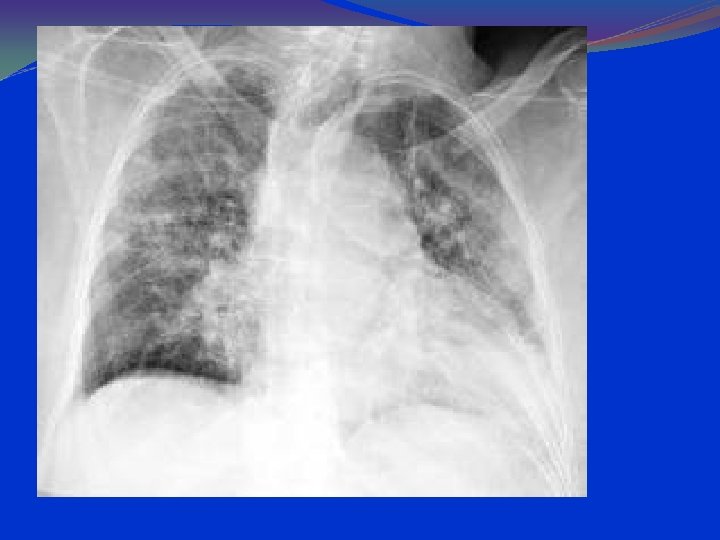

Atypical or Interstitial or viral Pneumonia In atypical pneumonia the x ray finding usually do not show lobar type of picture but meaning that the affection is restricted to small areas that is interstitial spaces between alveoli, rather than involving a whole lobe. As the disease progresses, however, the look can tend to be lobar pneumonia. There is also absence of leukocytosis. Extrapulmonary symptoms, give some clue to the causing organism.

Atypical or Interstitial or viral Pneumonia In atypical pneumonia : x ray chest infiltration, commonly begins in the perihilar region (where the bronchus begins) and spreads in a wedge- or fan-shaped fashion toward the periphery of the lung field. Reticular shadows as small linear striations running in all directions on which may be small white nodular appearance.

PCP: CXR Findings 90 -95% have pulmonary infiltrates. Combined interstitial & alveolar infiltrates. Predominantly at bases and centrally. Pneumothorax can be present. Lace like appearance.

PA Chest Radiograph Demonstrates bilateral, perihilar, R > L, ground glass opacities

PA Chest Radiograph Progressive disease showing extensive ground glass opacification with consolidation